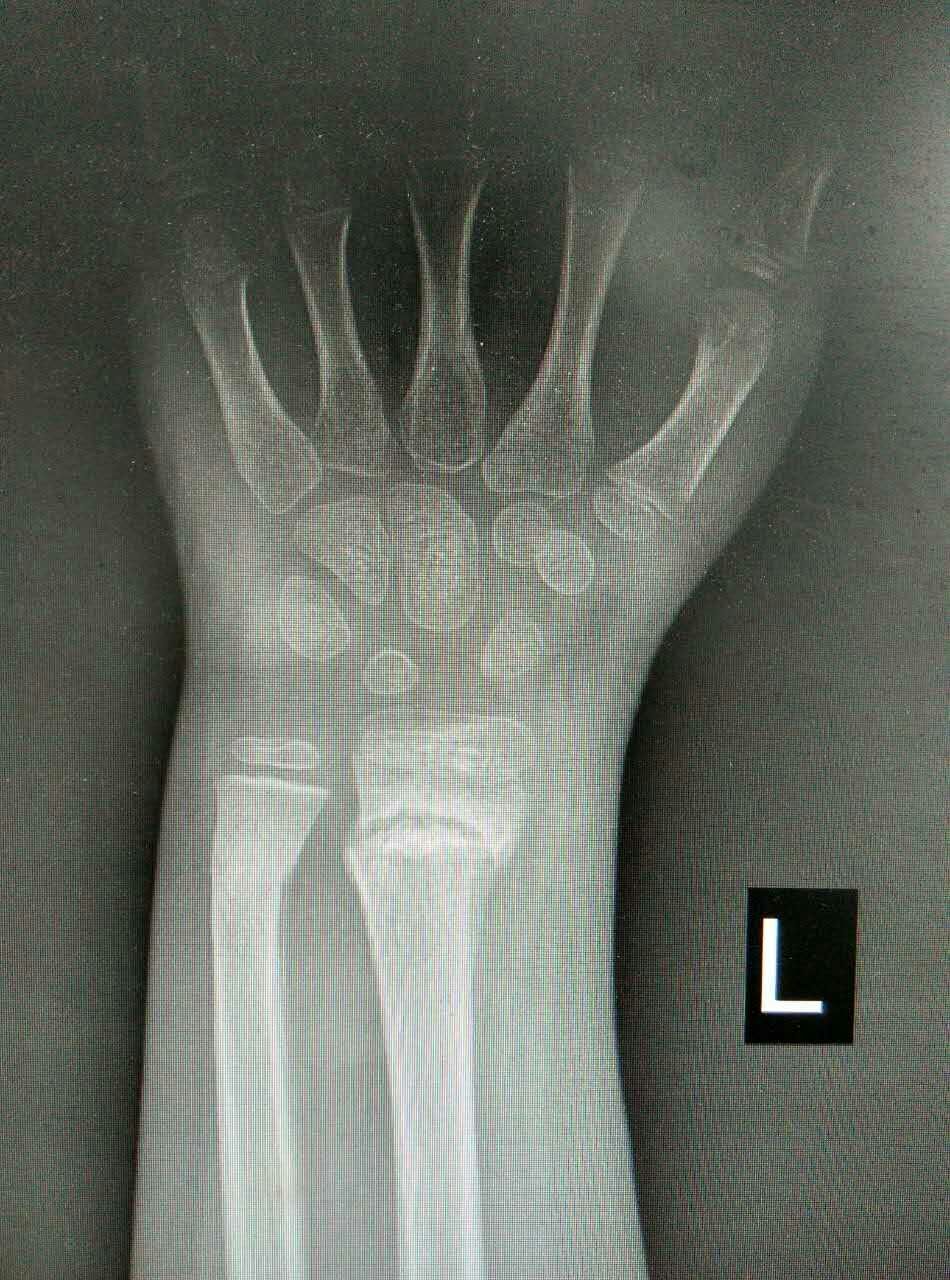

患儿,男,10岁,因左桡骨远端骨折畸形愈合5周来我院就诊。患儿家长曾在我市多家医院就诊,均认为切开复位,传统手术切口6-8cm。腕部血管、神经较多,共约20余条,稍有不慎,将给患儿造成较大后遗症,瘢痕永久存留,外观不美,且费用昂贵。我科谢瑞卿主任看过病人后决定采取微创闭合复位内固定,起初家属半信半疑,但后来经过耐心解释后决定在我院手术治疗。于2016-01-25在全麻下行左桡骨远端陈旧性骨折闭合复位内固定术,微创切口0.5cm左右,我们成功避免了各种意外事件的发生,截骨复位,我们巧妙应用骨刀在微创手术中的优点,成功闭合复位,术后复查拍片骨折复位满意。在骨科全体医护人员的积极治疗护理下,于春节前临床治愈出院。术后6周复查骨折已骨性愈合,腕关节功能良好。患儿家长万分感谢,赞叹西安凤城医院有如此精湛的技术和优质的服务质量与态度。

术后X光片